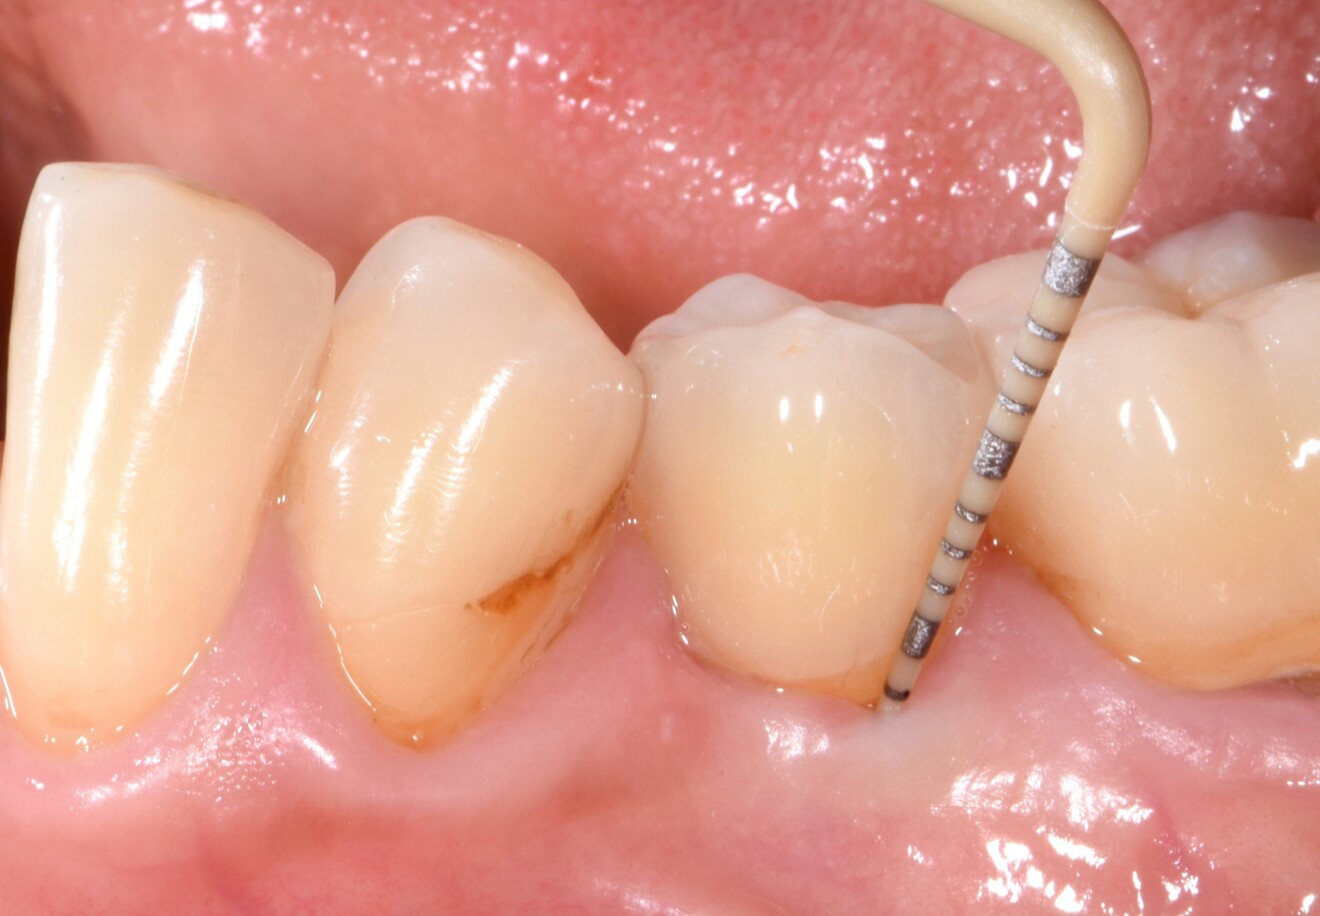

• À neuf ans de suivi, Patent Symbionic Teeth présentent une profondeur de sondage moyenne de 3 mm, conforme aux valeurs de référence d’une dent naturelle saine (Fig 3).¹

Fig. 3 : Après 4,5 ans de mise en fonction, Patent Symbionic Tooth affiche une profondeur de sondage maximale de 3 mm, valeur comparable à l’état physiologique d’une dent naturelle saine, témoignant de la stabilité des tissus environnants. (Photo : Dr Roland Glauser)